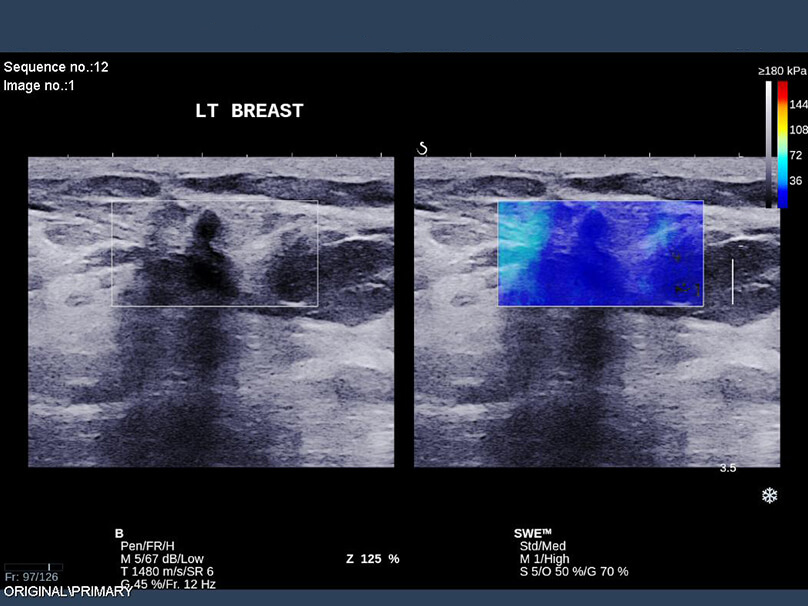

Περιπτώσεις ευρημάτων στο υπερηχογράφημα που μελετήθηκαν περαιτέρω με τεχνική ελαστογραφίας η οποία κατέγραψε μαλακό υπόστρωμα (μπλε χρώμα), που, στις περισσότερες περιπτώσεις, αφορά σε καλοήθεις καταστάσεις του μαστού, απομακρύνοντας ουσιαστικά το ενδεχόμενο της κακοήθειας.